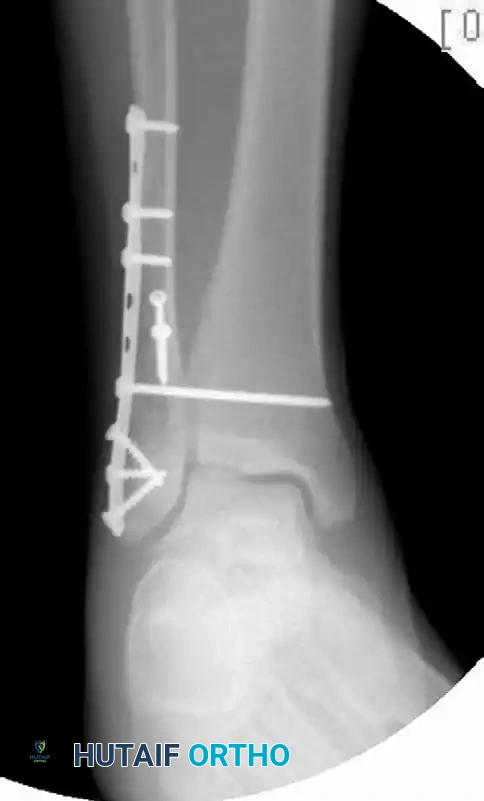

FIGURE 54-7 B: Postoperative AP/Mortise view. The fibula is anatomically reduced with a plate, and concentric tibiotalar reduction is restored and maintained with a single quadricortical syndesmotic screw.